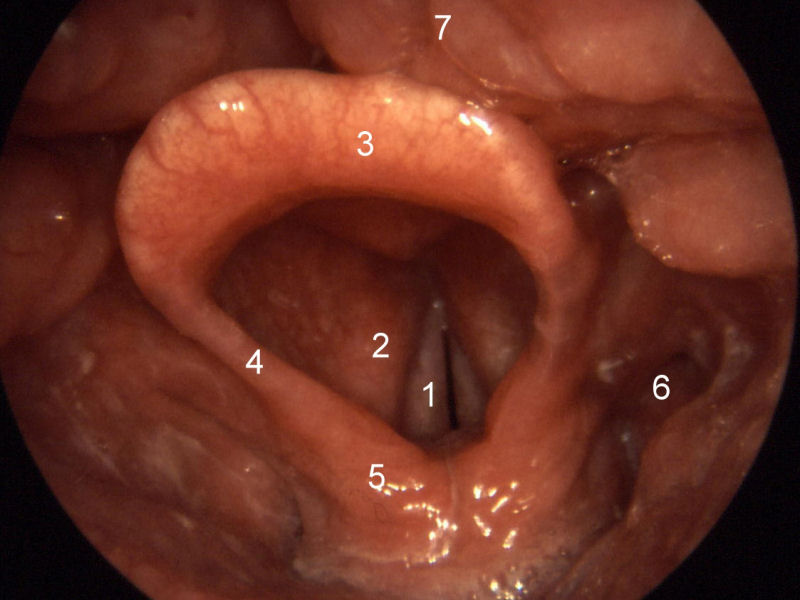

back normal larynx

Source: Larynx normal.jpg

Author: Welleschik